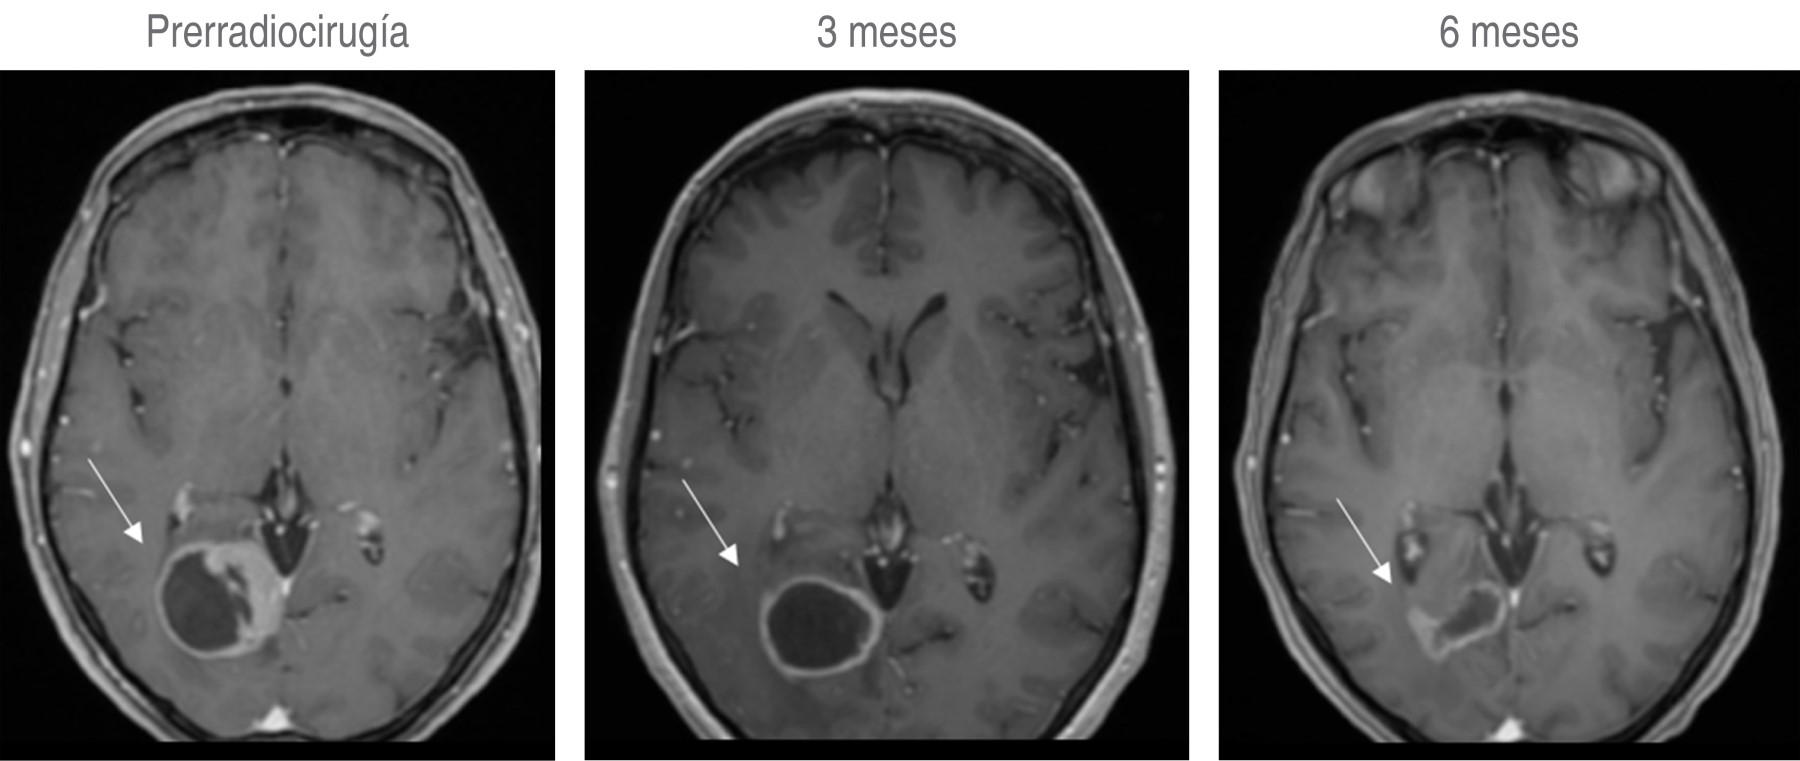

El primer tratamiento se realizó el 12 de noviembre del 2012 a una paciente con una metástasis cerebral por cáncer de mama con un buen control de la enfermedad local.

Desde el inicio de su funcionamiento y hasta el 28 de junio de 2019 se habían tratado un total de 867 casos. De éstos, 451 (52%) fueron tratados con radioterapia, 286 (33%) con radiocirugía craneal y 130 (15%) con radiocirugía extracraneal; cada año hemos logrado tener un mayor número de tratamientos. Las patologías más frecuentemente atendidas fueron: neoplasias 820 (95%), vascular 37 (4%) y funcional nueve (1%). De la patología neoplásica 689 (80%) fueron malignos y 131 (15%) benignos considerando el total de tratamientos. En la Figura 7 se observan ejemplos de pacientes tratados en la Unidad de Radiocirugía del Centro Médico ABC.